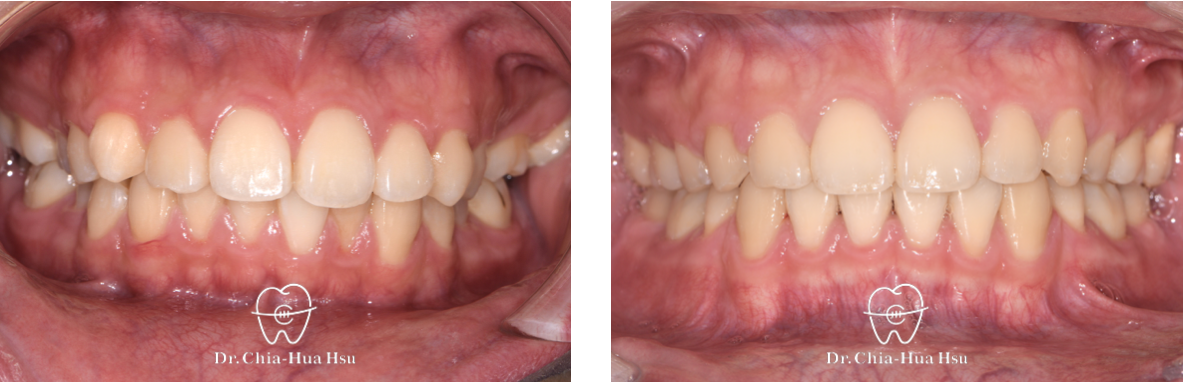

- 病患主訴:齒列擁擠、嘴微凸、中線偏移。

- 問題分析:患者嘴唇微凸、齒列擁擠、錯咬,而且中線偏移。

- 治療方式:拔除四顆小臼齒以獲取足夠空間,並使用傳統金屬矯正器搭配骨釘來退後上顎齒列並排齊牙齒。

- 治療時間:2 年 3 個月。

- 治療結果:改善齒列擁擠的問題,外觀也更好看,變成大帥哥!

治療前

治療後